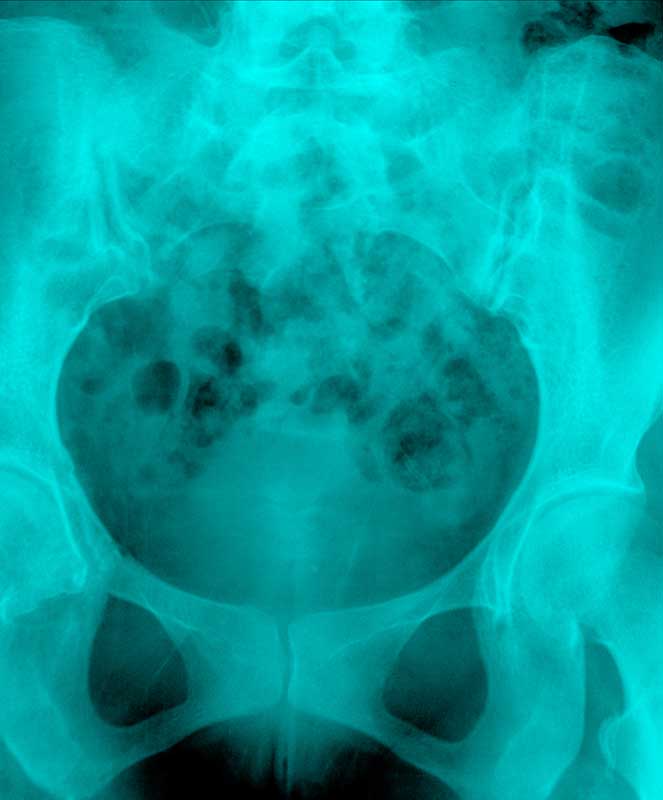

Hysterosalpingogram (normal) Image Fertility Tests Hysterosalpingogram The hysterosalpingogram (hsg) test is a diagnostic tool that plays a significant role in assessing female fertility. If you’re having trouble getting pregnant, your doctor might recommend a hysterosalpingogram (hsg) test to learn more about what might be causing the problem. A hysterosalpingogram (hsg) is done to: Hsg is an outpatient procedure that usually takes less than 5 minutes to. Fertility Tests Hysterosalpingogram.

Hysterosalpingogram HSG Fertility Test Illume Fertility